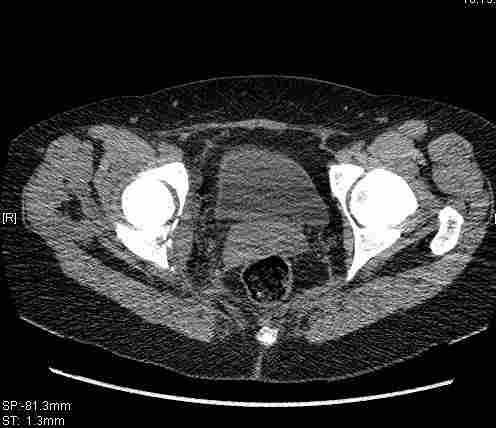

Re: Т-образный перелом вертлужной впадины

Удалось сегодня вывести пациентку в соседнюю больницу, где есть кт. Срезы сделаны только горизонтальные.